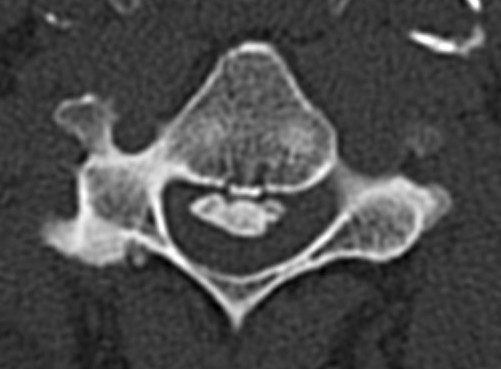

CT

Helps distinguish disc from osteophytes

- soft v hard disc

- diagnose OPLL

OPLL on CT

MRI and CT in same patient with OPLL